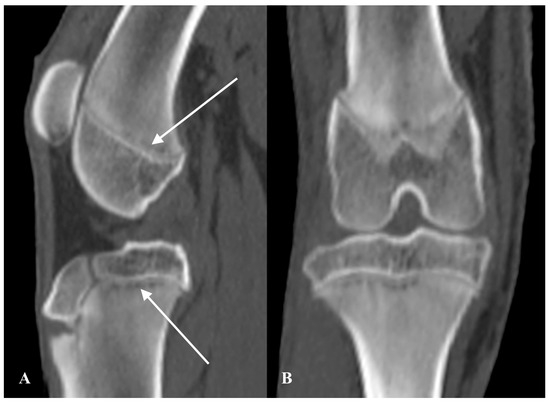

CT examination of the head and forelimbs was performed. Bilateral symmetrical metaphyseal changes were present in the proximal humerus, distal and proximal radius, distal ulna, and distal metacarpal bones. These changes were characterised by ill-defined, irregular hypoattenuating metaphyseal lytic bands parallel to the physis, with concurrent multiple rounded to semicircular hypoattenuating lesions with sclerotic centres (Figure 5A). An ill-defined sclerotic band parallel to the physis was also observed. Mild smooth paracortical new bone formation along the caudoproximal humeral metaphysis was present bilaterally. Mild dilation of the synovial joint with fluid was present at the shoulder and elbow bilaterally. In addition, several hypoattenuating rounded lytic lesions, some of which had a focal sclerotic centre, were present in the mandibular condylar processes bilaterally, extending to the articular surfaces (Figure 6). Moderate generalised superficial lymphadenomegaly was noted and was suggestive of a normal age-related finding or mild reactive hyperplasia. The CT findings in the appendicular skeleton were suggestive of MO with suspect concurrent involvement of the mandibles.

A repeat full-body CT scan before and after intravenous administration of iodinated non-ionic contrast medium was conducted. Similar ill-defined, irregular hypoattenuating lytic bands parallel to the physes were present, affecting the same metaphyses within the forelimbs. The previously described hypoattenuating metaphyseal rounded lesions were coalescing together in a more extensive and less defined lytic band. A mild smooth-to-spiculated periosteal reaction was present along the craniodistal aspect of the radial metaphysis. Similar metaphyseal changes were present in the hindlimbs, affecting the proximal and distal femur, tibia and fibula, and distal metatarsal bones bilaterally. Effusion within several joints was again noted, and diffuse subcutaneous fluid attenuation was present along the forelimbs and hindlimbs, suggestive of subcutaneous oedema or cellulitis. The mandibular condylar lytic lesions were reduced in size and less distinct. Moderate enlargement of several superficial and deep lymph nodes was present, along with mild pleural and peritoneal effusions, suggestive of inflammatory or age-related findings. The CT images were suggestive of mild progression of the suspected MO (Figure 5B).

Radiographs were performed to allow for future monitoring. Mediolateral views of the shoulders and orthogonal views of the carpi, stifles, and tarsi revealed bilateral metaphyseal lucent bands parallel to the physis in the proximal humerus, distal radius and ulna, distal femur, and proximal and distal tibia and fibula (Figure 5C). Perilesional sclerosis and moderate soft tissue swelling were also noted. The patient was discharged with medical treatment, with significant improvement in the clinical signs at one-month follow-up.

Figure 5. Case 4. Dorsal MPR images reconstructed with bone algorithm of the distal radius and ulna on CT at presentation (A) and after 5 weeks (B). Craniocaudal radiographic image of the distal radius and ulna at 5 weeks after presentation (C). In (A), an ill-defined, irregularly marginated lucent metaphyseal band parallel to the physis is present in the distal radius and ulna, with concurrent multiple rounded hypoattenuating lesions with sclerotic centres. In (B,C), the rounded lesions are less defined and coalescing together, forming a lytic band.